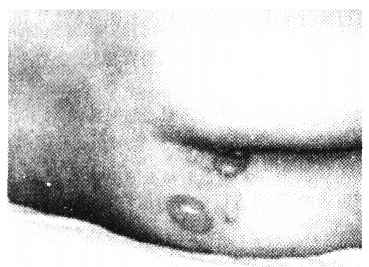

- 单项选择题患者男,72岁,下肢瘫痪,为其翻身时发现受压局部皮肤如图所示(见文末彩图),该临床表现是压疮的

- 1、此表现属哪一期压疮2、护士护理该创面